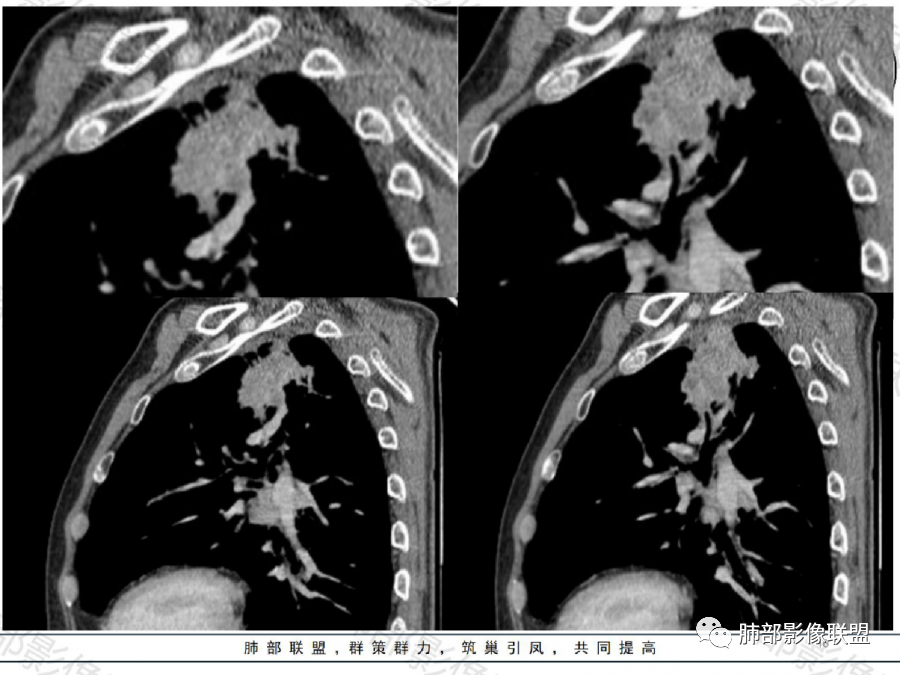

影像表现特点:左肺上叶纵隔旁主动脉弓上方实性肿块影,不规则,膨胀性生长,有棘状突起及收缩,肿块内密度不甚均匀,隐约见小钙化灶。周围具有一定的分叶及长短不一的毛刺征象,外围有小斑片影。矢状位显示支气管截断。增强扫描病灶不均匀强化,内部见小片状的坏死,呈典型的“沼泽样”改变。总体分析恶性征象更多。支持肺癌-鳞癌,支气管截断具有强烈提示意义。